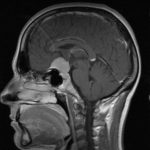

Cette masse peut entrainer notamment :

- Une irritation du cerveau qui se manifeste par une épilepsie

- Une compression voire destruction d’une partie du cerveau causant un affaiblissement ou une perte d’une fonction du cerveau

- Une augmentation de la pression à l’intérieur du crâne (espace inextensible à l’intérieur duquel vient s’ajouter le volume de la tumeur), ce qui va se manifester initialement par des maux de tête d’aggravation progressive qui vont s’associer à des nausées, des vomissements, des troubles visuels… Cet état peut aboutir à la perte de la vue dans les formes d’évolution lente et au décès dans les formes d’évolution rapide.